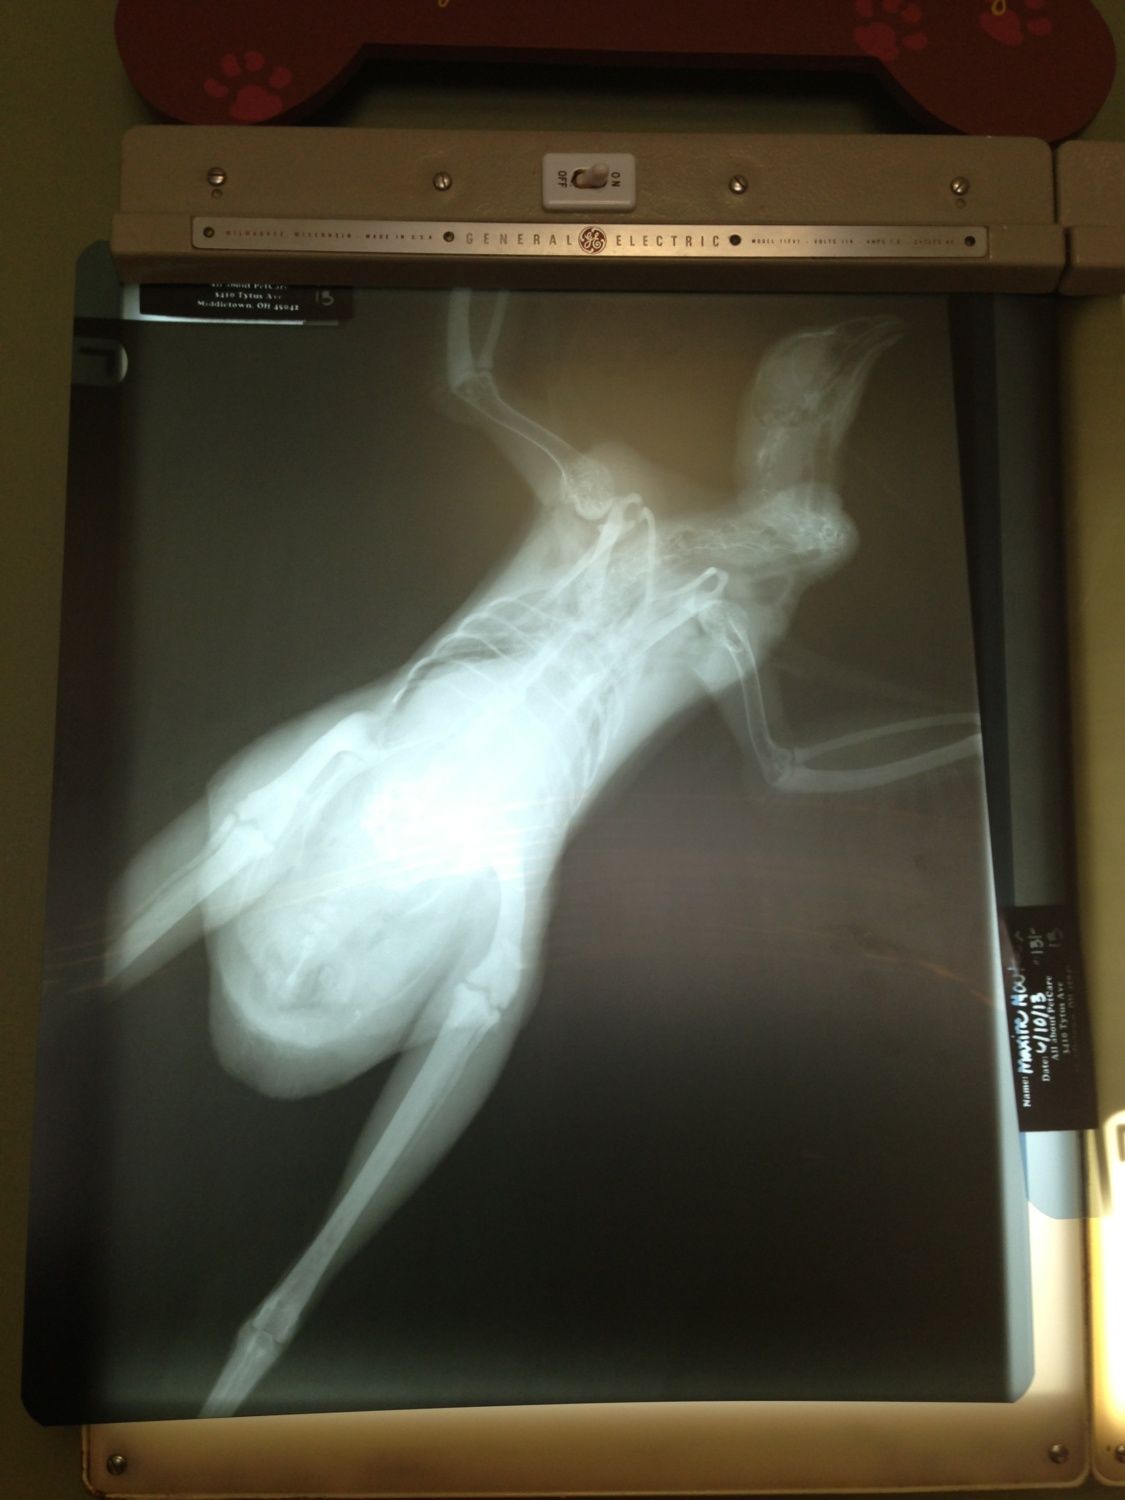

I just wanted to share and ask for thoughts and prayers if you are willing, for my Maxine. I thought she was egg bound, but she ended up laying an egg right before we headed out to the vet. She is swollen below her vent. Eating and drinking and acting normally. We had x-rays and she is staying the night for barium enema studies and blood work.

We are just waiting to hear what the barium study shows. I love this girl so much!!!